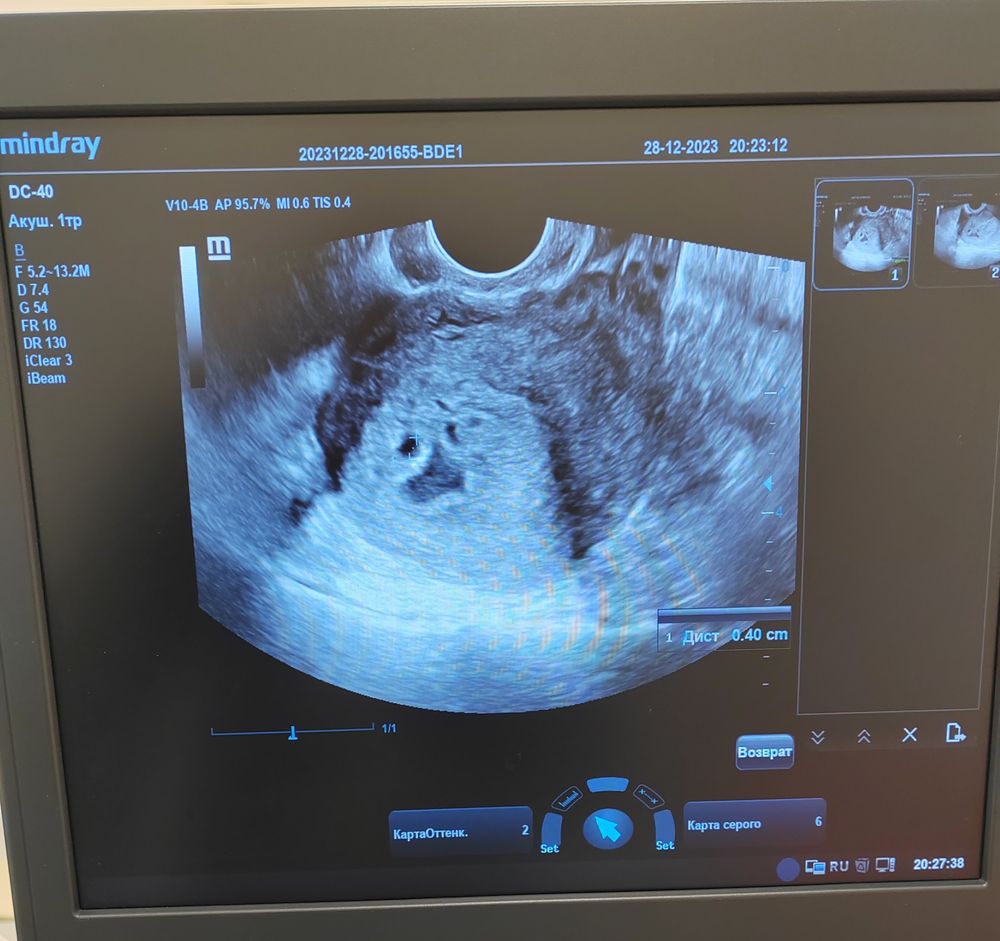

Мажущие выделения, не совпадает срок Б

Мама мальчика (2 года) Нижний Новгород

Если за столько дней плодное яйцо выросло на два мм, то дела явно плохи. С другой стороны первое узи странное